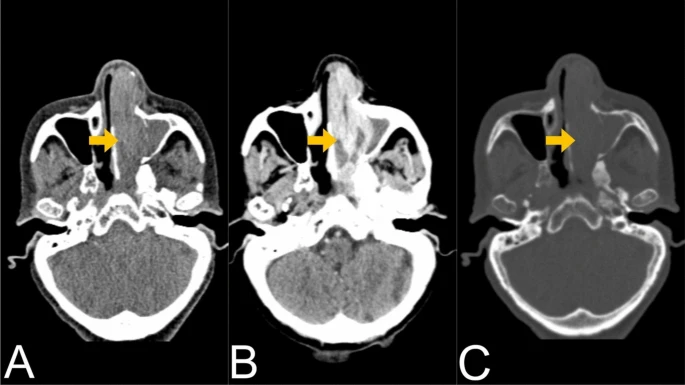

All laboratory examinations were within normal limits. A CT scan of the paranasal sinuses revealed an enhancing soft tissue mass infiltrating the left nasal passage and ethmoid air cells measuring approximately 7.3 × 2.5 × 2.8 cm in size with associated nasal occlusion and obstruction of the ipsilateral osteomeatal complex and sphenoethmoidal recess leading to maxillary and sphenoid sinus opacification. The medial aspect of the inferior orbital wall as well as the left medial maxillary sinus wall were destroyed. Regional lymphadenopathy was not visible. The patient was classified as stage IVA by the American Joint Committee on Cancer (AJCC).